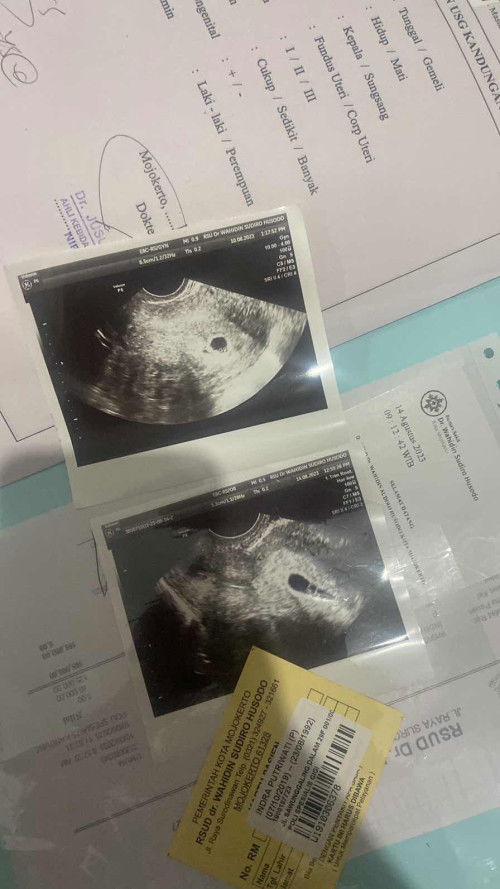

Moms ini normal apa tidak bentuknya gini?

Moms , ini usg saya yg atas itu sekitar 4 harian yg lalu , terus yg bawah hari ini . Menurut moms bentuk lonjong seperti ini normal kah ? Saya takut jadinyaaa 🥹